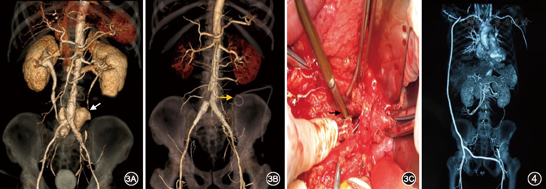

2例患者未发现明显诱因,其余8例患者存在可能的感染源。其中4例发现AEF(1例为小肠镜检查确诊)(图2);3例EVAR术前即有发热表现,并且增强CT显示瘤体不规则、瘤壁增厚、瘤体周围呈现明显炎性反应等炎性腹主动脉瘤特征,再次手术过程中也给予了证实(图3);1例此次发病前有明确的上呼吸道感染及败血症病史。

1例患者放弃二次手术,1例因耐受力较差故仅行清创引流术,7例行腋动脉——双侧股动脉人工血管旁路+支架切除+清创术,1例行双侧腋动脉——股动脉人工血管旁路+支架切除+清创术,手术均为Ⅰ期完成并获得成功。手术步骤为先建立解剖外人工血管旁路,然后经腹部正中切口显露腹主动脉,于肾动脉开口上方或膈下水平临时阻断腹主动脉,纵行切开瘤体前壁并取出支架,二次手术中移除支架后发现腹主动脉瘤右侧壁溃疡(图2A),清理后显示空肠中段2 cm直径瘘口(图2B),随后将阻断钳移至肾动脉水平以下,并以3-0及4-0尼龙线双重连续缝合腹主动脉残端以及髂动脉残端。尽量清除瘤壁组织及瘤腔内容物,缝扎腰动脉开口。由于可用材料有限,本组病例均采用解剖外人工血管旁路来重建下肢血运(图4)。创面以0.5%碘伏溶液反复浸泡3次,每次10 min,随后以大量生理盐水冲洗创面并留置思华龙引流管。

炎性动脉瘤也可能是导致EVAR术后支架感染的原因之一,既往文献报道罕有谈及。本组病例中有3例在EVAR术前就存在发热、血液白细胞计数增高以及瘤壁增厚、瘤体不规则、瘤体边界模糊等CT征象,高度怀疑炎性动脉瘤,3例均在EVAR术后住院期间即出现发热症状,在再次手术过程中也证实了这一判断(图3)。对于疑似炎性动脉瘤的患者,不宜首选EVAR手术,即便在紧急情况下为挽救生命而被迫进行腔内治疗,也应及时进行后续的清创、引流等彻底处理。

重建下肢血供的常用方法包括解剖外人工血管旁路和原位重建。解剖外旁路因无需经过感染创面,所以发生再次感染的可能性相对较小,此外具有创伤小、材料简单、可分期进行等优点,一直以来都是处理腹主动脉移植物感染的理想术式,但同时也存在远期通畅率低的缺点因此有人更青睐于原位重建[5,12]。多数人认为应该根据患者的具体情况、能够利用的材料以及术者的技术特长等进行合理的术式选择[3,8]。由于可用材料有限,本组病例均采用解剖外人工血管旁路来重建下肢血运(图4)随访期间解剖外旁路通畅率达87.5%。